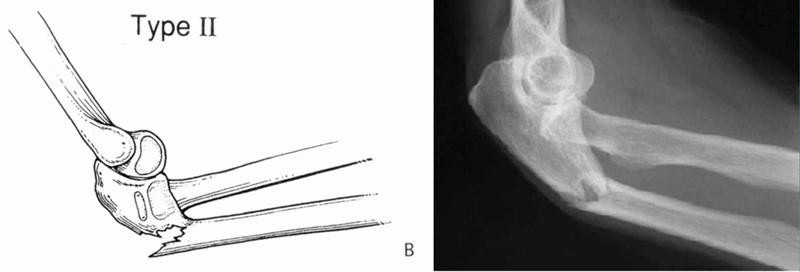

Ⅱ型(屈曲形):桡骨头后脱位或后外侧脱位,尺骨干骨折端向后成角,约占10%~15%。

受伤机制:沿前臂长轴向近端传导的应力,在屈曲肘关节时,引起尺骨后侧皮质断裂,在尺骨干骨折端向后成角。